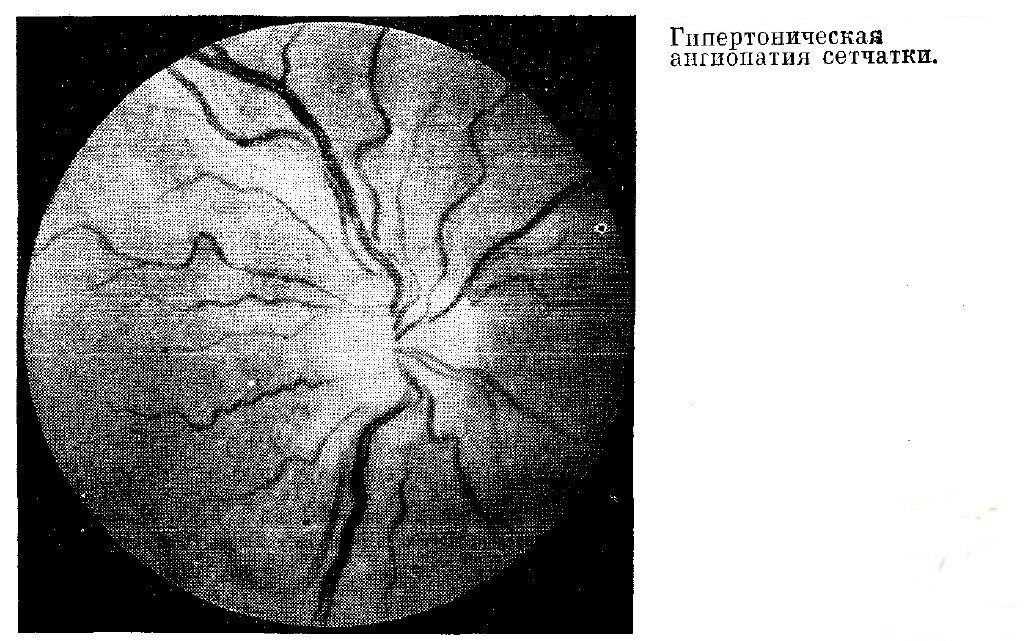

Для оценки изменений глазного дна, обусловленных артериальной гипертензией, используют классификацию, предложенную М. Л. Красновым, согласно которой выделяют три стадии изменений сосудов сетчатки. Первая стадия — гипертоническая ангиопатия — характерна для I стадии гипертонической болезни — фазе функциональных сосудистых расстройств. В этой стадии происходят сужение артерий и расширение вен сетчатки, соотношение калибра этих сосудов изменяется до 1:4 вместо 2:3, отмечаются неравномерность калибра и увеличение извилистости сосудов, может наблюдаться симптом артериовенозного перекреста I степени (симптом Салюса-Гунна). Примерно в 15% случаев в центральных отделах сетчатки имеет место штопорообразная извилистость мелких венул (симптом Гвиста). Все эти изменения обратимы; при нормализации артериального давления они регрессируют.